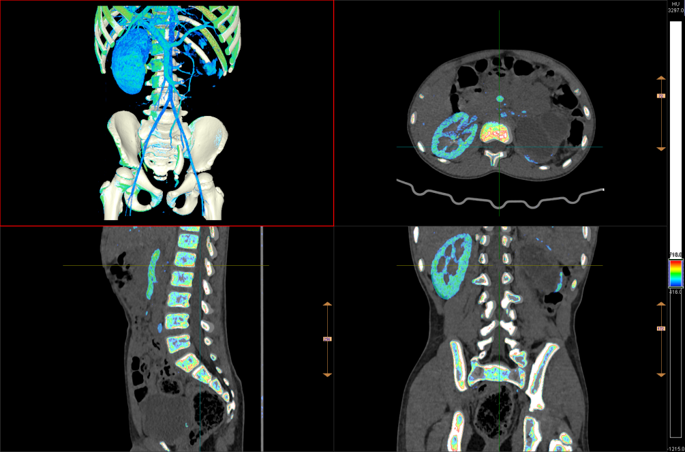

多模态融合手术规划与术后评估方案能支持多种设备类型、多序列及功能像与解剖像融合,提供全面解剖与代谢信息,精准定位病灶,继而完成三维重建、手术路径模拟及入路优化设计,评估血管、神经等重要脏器组织的潜在风险,提升复杂病例手术精度。